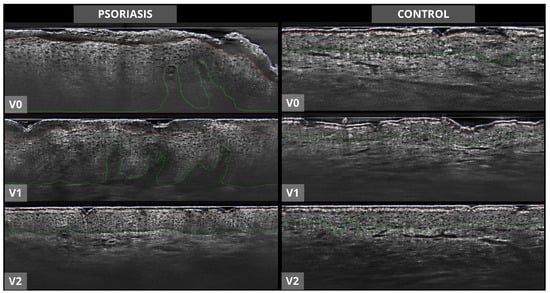

The segmentation of the skin layers and detection of hair follicles was visually supervised by an expert team to ensure validated results. All 3D stacks with a variation of more than 30% between manually and AI model-generated measurements were reviewed by an expert team to detect possible reasons for differences or wrong measurements. The number of pixels between the blue and red line (see Figure 2 and Figure 3) divided by the number of pixels corresponding to the region of interest was used for calculating the SC thickness (SCT). The result in microns was obtained with the pixel–micron equivalence. The same procedure was used for the ET, calculating the number of pixels between the red and green line and summing up the SCT. DEJ undulation was quantified as the ratio of the DEJ contour length to the straight-line length of the analyzed area in percent. In acquisitions without visible DEJ, because of excessive acanthosis, the AI model placed the green line at the bottom of the stack. For each parameter, the area detected as a follicle by the follicle detection model was excluded from the calculation in order to prevent a bias of the skin layer measurements.

Figure 2.

The artificial intelligence (AI) model segmented line-field confocal optical coherence tomography stacks (only the vertical view within the 3D stack depicted here, LC-OCT image size: 1.2 mm × 0.4 mm) of study plaque (left side) and control area (right side). Blue line = skin surface; red line = boundary between stratum corneum and stratum granulosum/living epidermis; green line = before dermo-epidermal junction. V0 = before therapy, V1 = after 4 weeks of therapy, V2 = after 12 weeks of therapy.